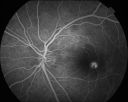

AVM522 viewsRF of AVM in OS of a 48 yr old female.Mar 11, 2014